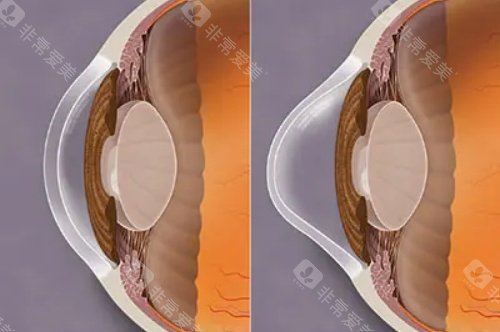

使用特殊的仪器去除角膜上皮,再滴入核黄素眼药水,使角膜充分吸收。

使用紫外线照射角膜,促进角膜胶原纤维交联,增强角膜的强度。